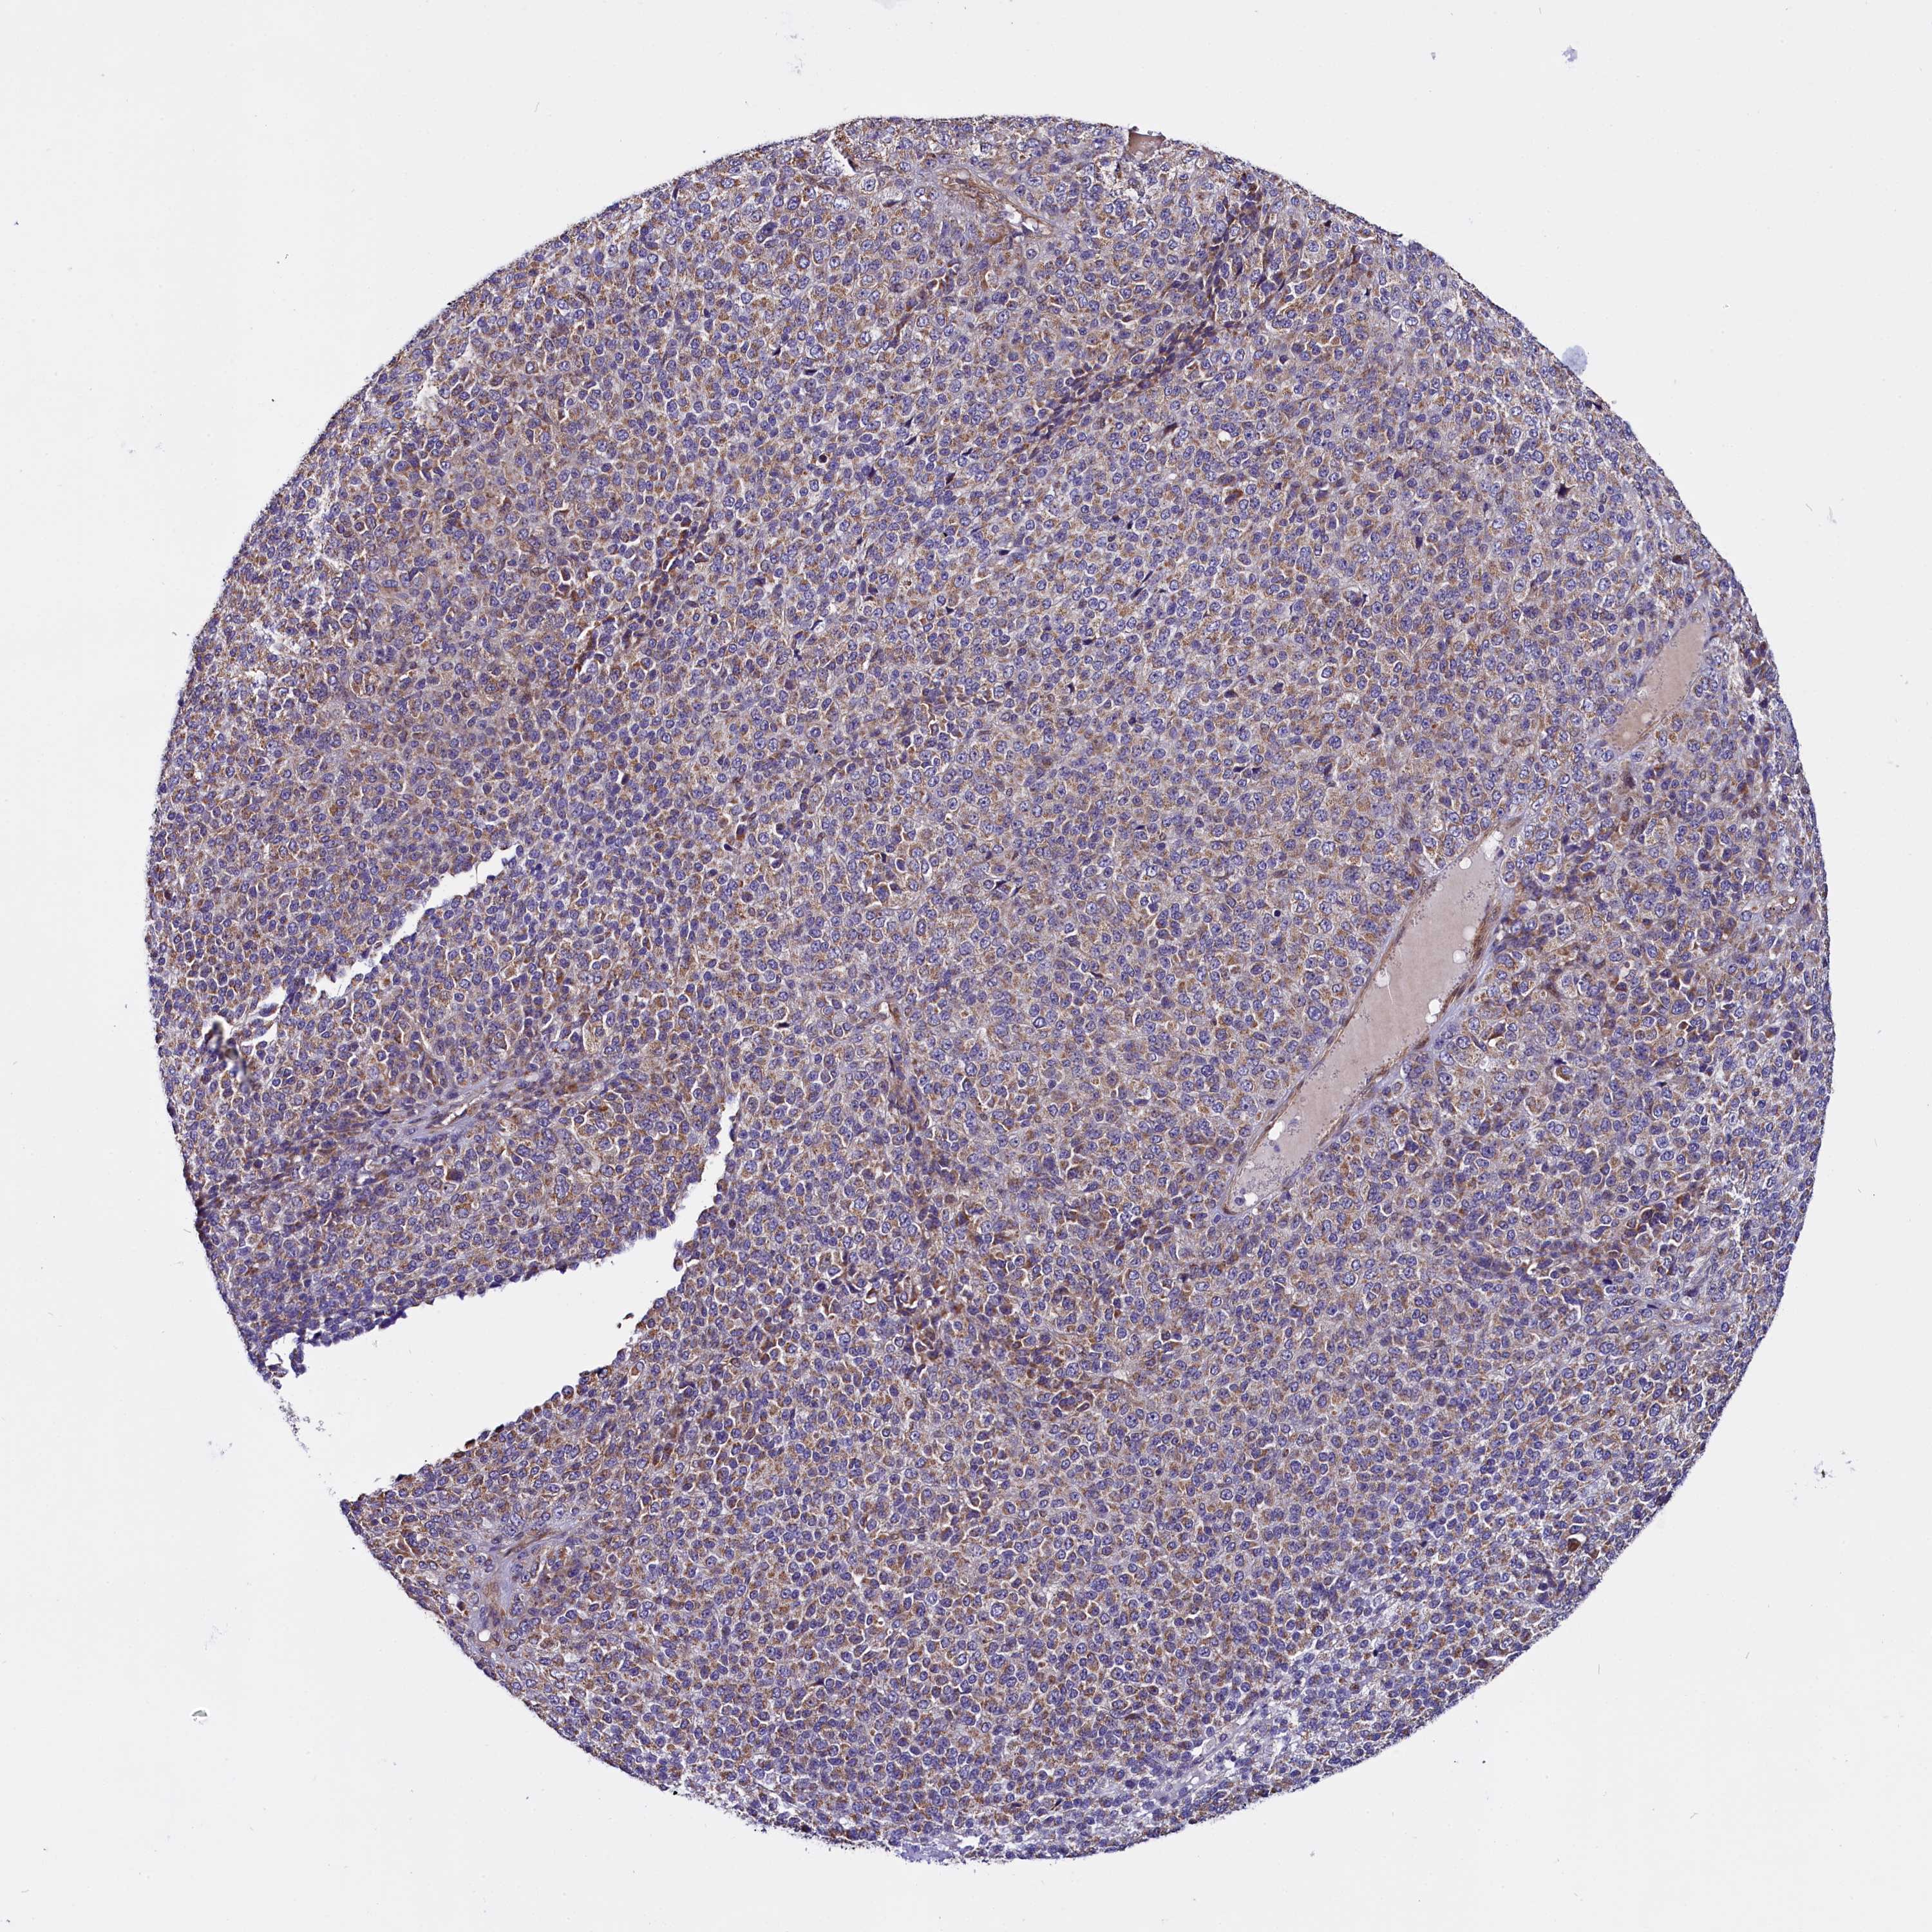

MELANOMA - Protein expressioni

A mouse-over function shows sample information and annotation data. Click on an image to view it in a full screen mode. Samples can be filtered based on level of antibody staining by selecting one or several of the following categories: high, medium, low and not detected. The assay and annotation is described here.

Note that samples used for immunohistochemistry by the Human Protein Atlas do not correspond to samples in the TCGA dataset.

Antibody stainingi

Antibody staining in the annotated cell types in the current human tissue is reported as not detected, low, medium, or high, based on conventional immunohistochemistry profiling in selected tissues. This score is based on the combination of the staining intensity and fraction of stained cells.

Each image is clickable and will lead to virtual microscopy that enables deeper exploration of all samples and also displays staining intensity scores, fraction scores and subcellular localization as well as patient and tissue information for each sample.

Antibody HPA041412

Antibody HPA056006

Staining

High

Medium

Low

Not detected

Intensity

Strong

Moderate

Weak

Negative

Quantity

>75%

75%-25%

<25%

None

Location

Nuclear

Cytoplasmic/membranous

Cytoplasmic/membranous,nuclear

Malignant melanoma, NOS

Malignant melanoma, Metastatic site